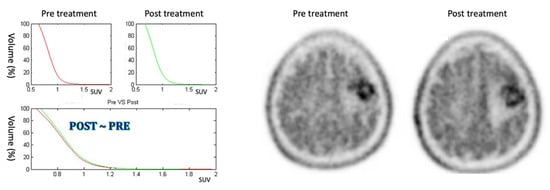

3.1. Positive Response

Nine patients who showed positive responses to treatment show a reduction in the AUC greater than about 10% and a shifting of the CSH to the left, as is possible to see in Figure 6 (patient #3). Patients included in this category show a marked response to the therapy. In particular, all cases show a reduction in the MET uptake (as can be seen in Table 1, where ΔSUVmean is always negative), indicating a probable formation of necrotic areas.

Figure 6.

On the left: CSH pretreatment (top left); CSH post-treatment (top right); comparison between pre- and post-treatment (bottom) in positive response case: ΔAUC = −59.05%. On the right: PET images of pre- and post-treatment. (For interpretation of the references in colour in this figure legend, the reader is referred to the web version of this article.)